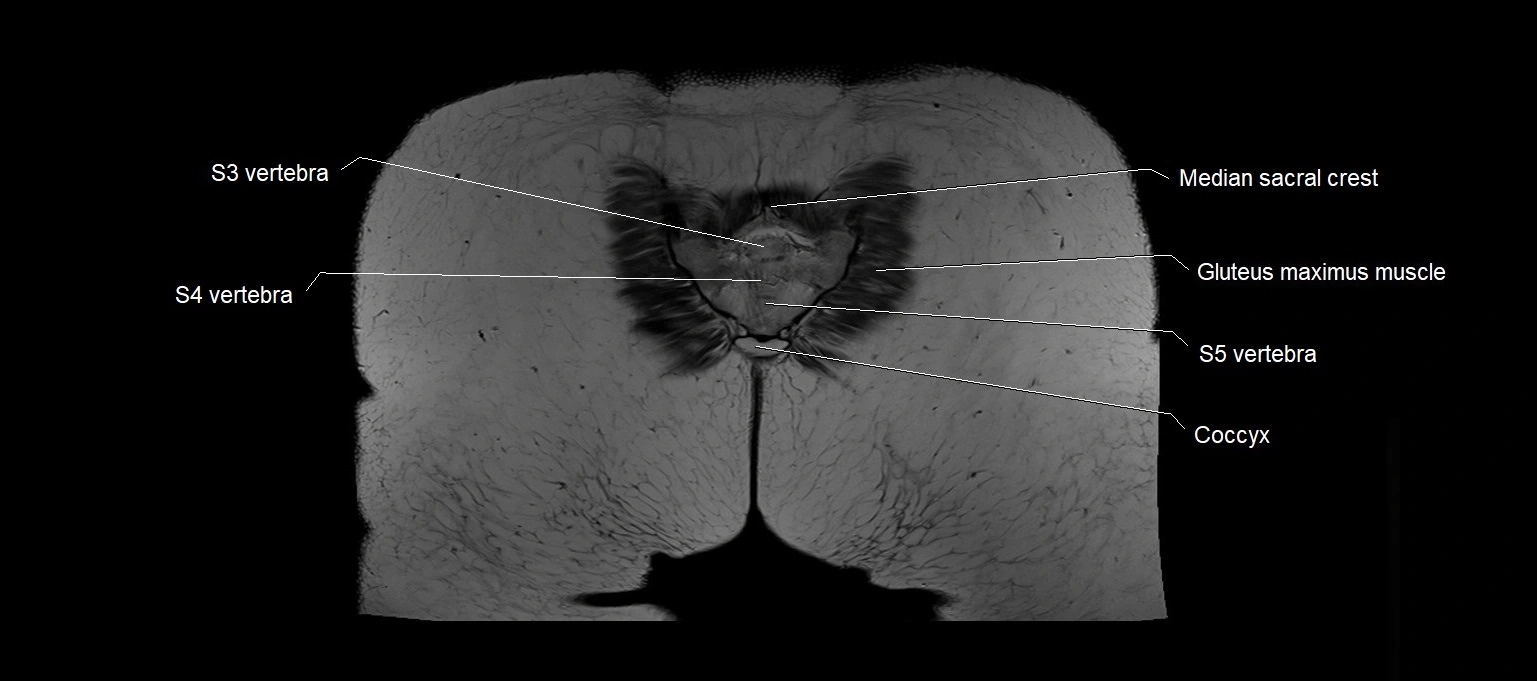

MRI images